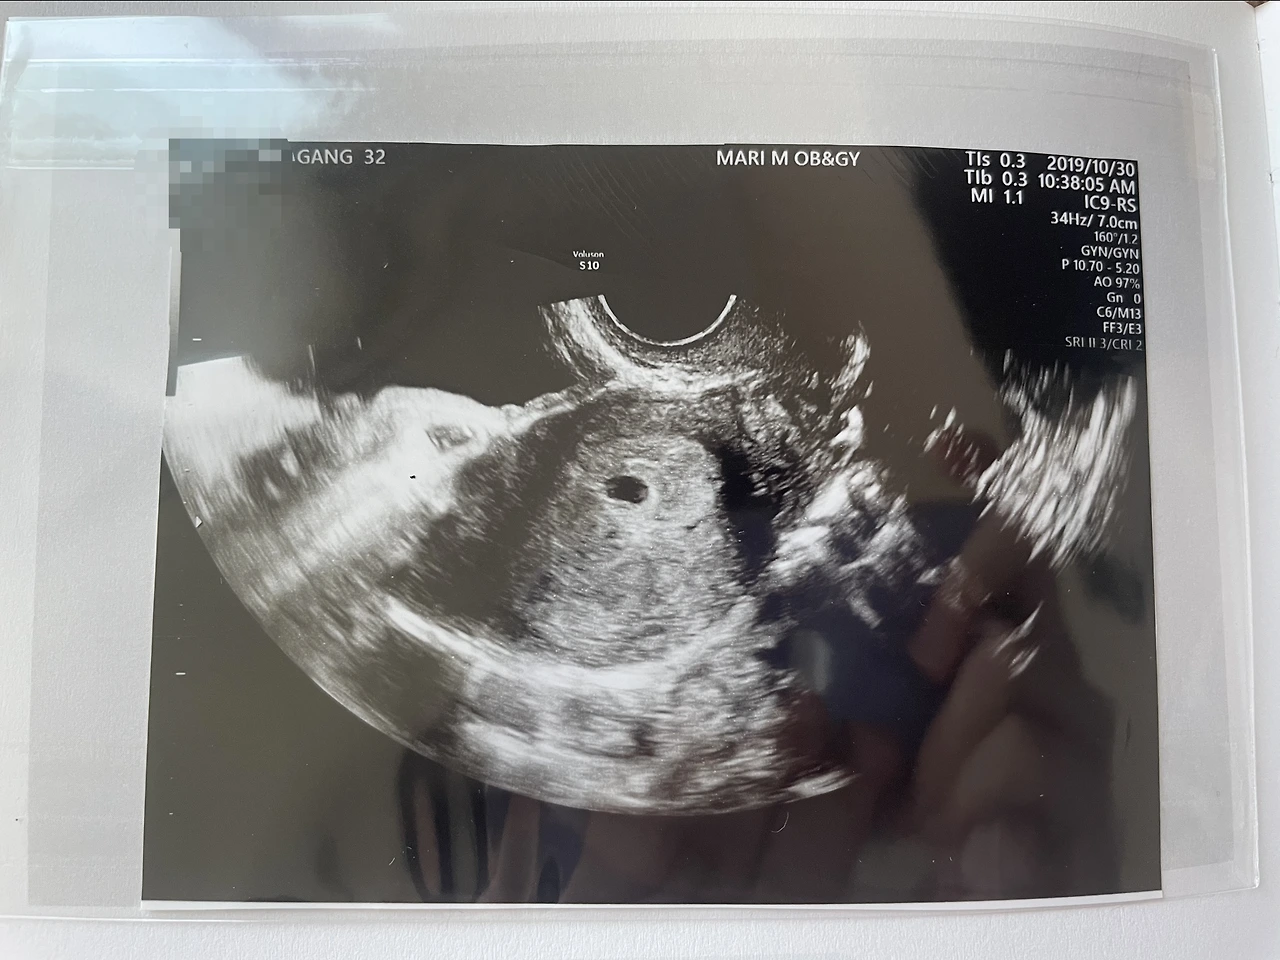

저 까만콩이 아기집이다.

그러나 막상 병원에 가서 초음파를 보는 순간 선생님이 이게 아기집이에요. 임신 맞습니다. 하시기에 화면을 보는데 순간적으로 막 울컥하며 '진짜 아기가 왔구나 ' 싶었다. 기쁨이 차오르고 정말 눈물이 나오는 감격 하면 눈물이 나온다는 사실을 처음으로 알았다. 바로 친정엄마한테 전화해 소식을 전하며 회사로 돌아가는 그 길은 평생 못 잊을 순간이었다.

꼼꼼한 우리남편 초음파사진정리중